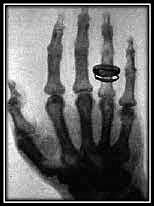

Descubrimiento de los Rayos X

El físico alemán Wilhelm Conrad Roentgen descubrió los rayos X mientras realizaba experimentos con tubos de vacío y un generador eléctrico.